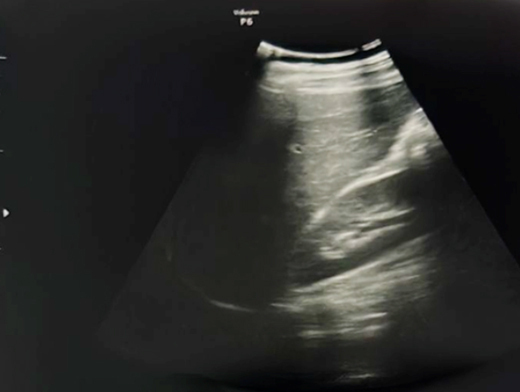

Mme G. est finalement césarisée sous anesthésie générale sans complication. Lors de l’hystérotomie, le liquide amniotique est sanglant avec de nombreux caillots. Les pertes sanguines sont estimées à 1 500 mL. L’équipe d’anesthésie a administré en peropératoire un culot de globules rouges et un plasma frais congelé (PFC), ainsi que de l’acide tranexamique. L’utérus est tonique en fin d’intervention. Au cours de la surveillance en salle de surveillance post-interventionnelle (SSPI), à quatre heures postopératoires, Mme G. a une barre épigastrique résistante aux antalgiques de palier 3. Les constantes sont les suivantes : pression artérielle = 190/110 mmHg ; fréquence cardiaque = 120 bpm ; saturation en oxygène = 99 % en air ambiant. Compte tenu de la tachycardie, vous réalisez une échographie transabdominale dont les images sont les suivantes. Figure 2a (Rodolphe Matias de Sousa, La Revue du Praticien)Figure 2b (Rodolphe Matias de Sousa, La Revue du Praticien)Figure 2c (Rodolphe Matias de Sousa, La Revue du Praticien) Vous décidez d’avancer le prochain bilan biologique et récupérez les résultats suivants : hémoglobine = 8,7 g/dL ; plaquettes = 40 G/L ; TP = 65 % ; TCA = 1,02 ; fibrinogène = 2 g/L ; haptoglobine indosable ; ASAT = 260 UI/L ; ALAT = 240 UI/L.

Concernant l’hématome sous-capsulaire du foie : Tableau 3 (Rodolphe Matias de Sousa, La Revue du Praticien) Concernant l’échographie transabdominale à la recherche d’un hémopéritoine :on regarde deux espaces, le cul-de-sac de Douglas entre l’utérus et le rectum, et l’espace de Morrison entre le foie et le rein. Figure 3a (Rodolphe Matias de Sousa, La Revue du Praticien)Figure 3b (Rodolphe Matias de Sousa, La Revue du Praticien)Figure 3c (Rodolphe Matias de Sousa, La Revue du Praticien) Pour rappel, concernant l’échographie en gynécologie : Figure 4a (Rodolphe Matias de Sousa, La Revue du Praticien)Figure 4b (Rodolphe Matias de Sousa, La Revue du Praticien)Figure 4c (Rodolphe Matias de Sousa, La Revue du Praticien)Figure 4d (Rodolphe Matias de Sousa, La Revue du Praticien)Figure 4e (Rodolphe Matias de Sousa, La Revue du Praticien)Figure 4f (Rodolphe Matias de Sousa, La Revue du Praticien)Figure 4g (Rodolphe Matias de Sousa, La Revue du Praticien)Figure 4h (Rodolphe Matias de Sousa, La Revue du Praticien)Figure 4i (Rodolphe Matias de Sousa, La Revue du Praticien)